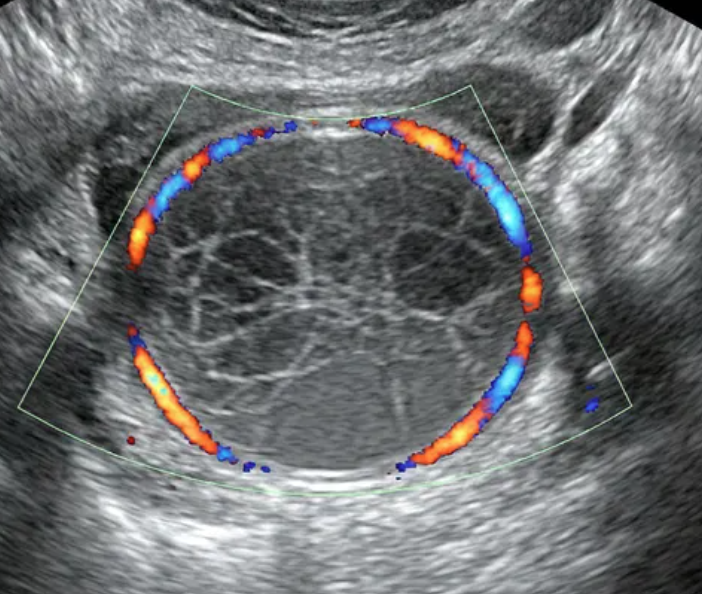

O-RADS US 4 — Risco Intermediário

Risco: 10-<50%Cisto multilocular sem componente sólido ≥ 10 cm ou com IC = 4, cisto unilocular/multilocular com componente sólido, lesão sólida com superfície lisa e IC = 2–3.

Cisto multilocular, sem componente sólido

Cisto unilocular com componente sólido

Cisto multilocular com componente sólido

Lesão sólida

Conduta

Opções de imagem incluem US com especialista (se disponível) e RM (com O-RADS MRI score), de acordo com o protocolo do ginecologista-oncologista. Atendimento pelo ginecologista com consulta ao ginecologista-oncologista ou exclusivamente pelo ginecologista-oncologista.

O-RADS US 5 — Alto Risco

Risco: ≥50%Cisto unilocular com ≥ 4 projeções papilares, cisto multilocular com componente sólido e IC = 3–4, lesão sólida com IC = 4 ou superfície irregular, presença de ascite e/ou nódulos peritoneais.